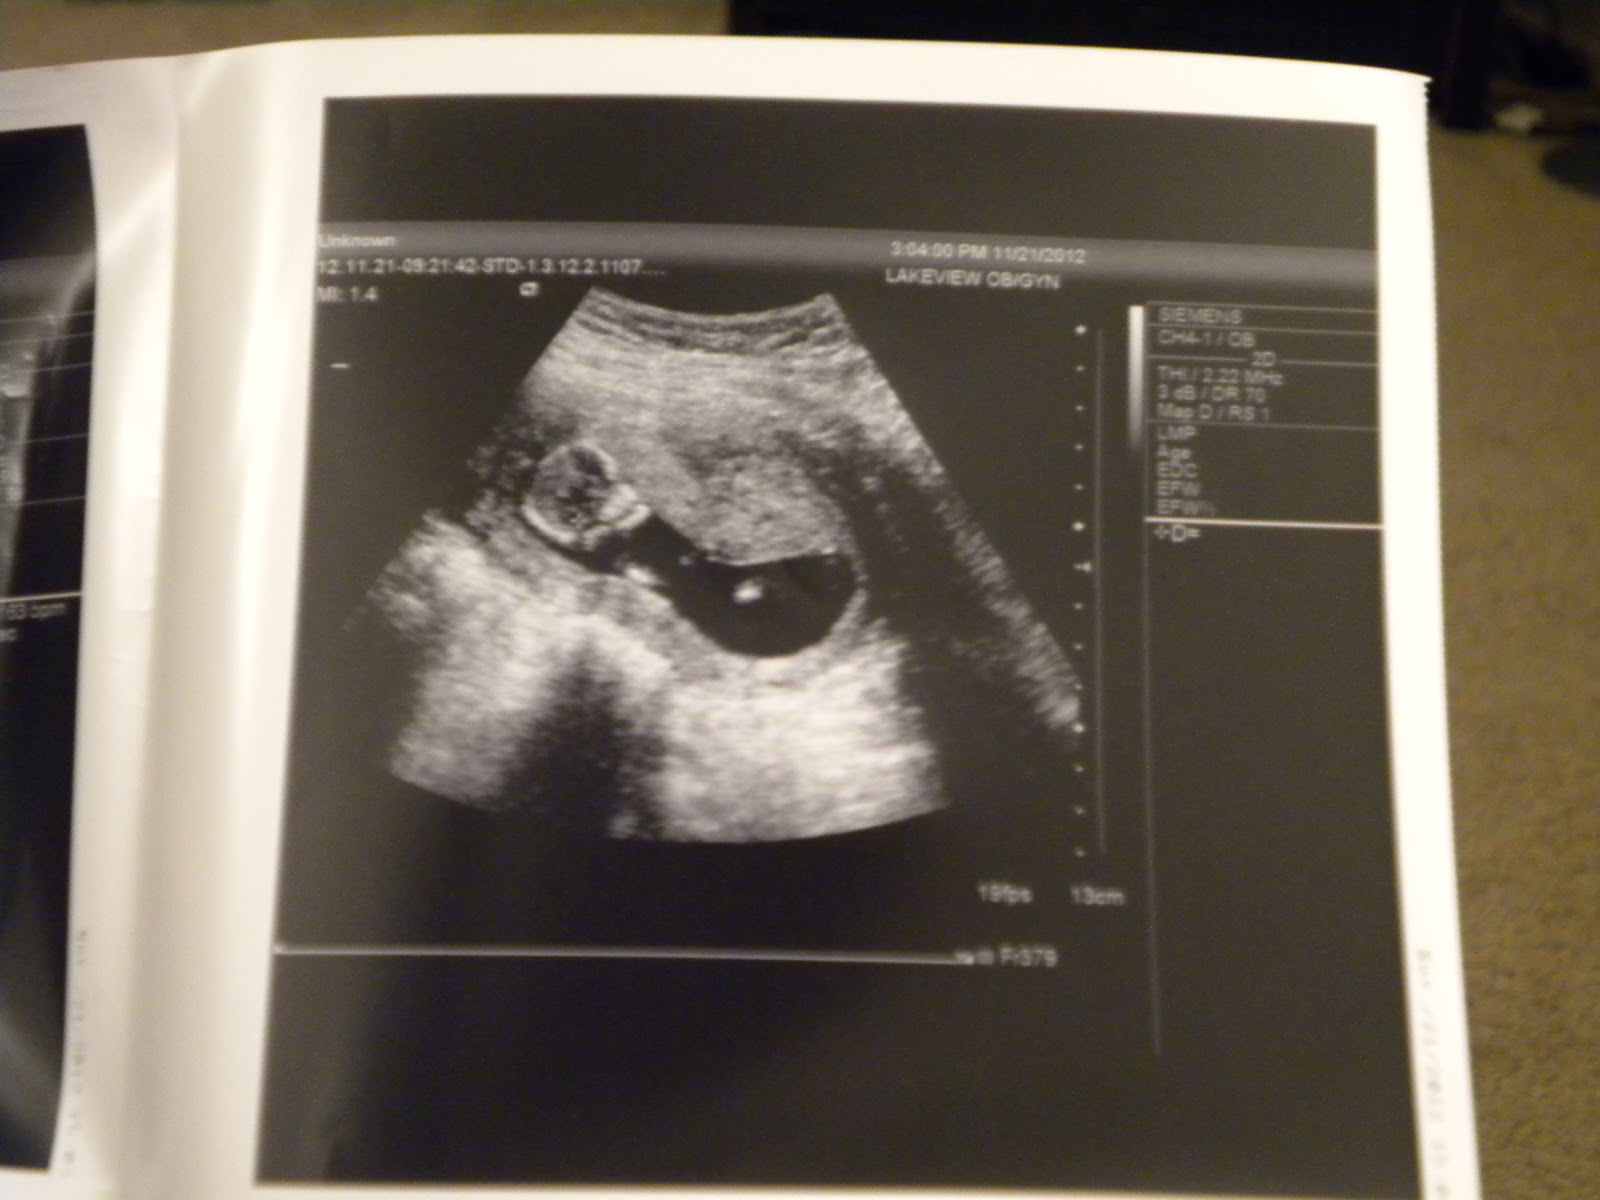

And here is today's ultrasound!!

Can you see it's little face?? I just wish that the doctor had gotten a good pic of the whole body!

This pic isn't as clear but if you imagine from the last ultrasound from today, just picture the babies hand in front of it's face! It was clear as day on the monitor but didn't translate to a pic as well as I'd hope!

This ultrasound was amazing! We got to see all of baby. And it looks human! fully formed and adorably tiny! About the size of a medium shrimp now! While the doctor was doing the ultrasound, she was trying to get the heartbeat and the baby wouldn't hold still! Seriously boogying around! Bryce and I were so excited to see our little one moving around like that!!

Baby's heart beat was 163, a little bit slower than last time but still strong and perfect!

Here is the catch... My due date WAS June 6th... NOW IT IS MAY 30TH!!! Ok I realize that it's only 1 week, but it is MAY! What if baby comes a week early and is literally born on Coen's birthday!?!

Apparently the biggest measurement of our last visit was accurate and I'm further along than expected...

Our next appointment is December 20th and she is hopeful that we'll be able to find out what we're having! I'll be 17 weeks along and typically you can find out between 16-19 weeks!